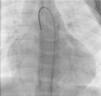

The most frequent symptoms were murmur and/or fatigue. All fistulas were congenital. Five patients (42%) had concomitant cardiac disease: pulmonary atresia with intact ventricular septum (1), patent ductus arteriosus (1), ostium secundum atrial septal defect (1), stenotic bicuspid aortic valve (1), and critical pulmonary stenosis operated in the neonatal period (1). Selective angiography was performed to delineate the anatomy of the fistula(s), which were embolized in the most distal part, sparing all the collateral branches. In one patient an arteriovenous loop was formed through the fistula, embolizing the terminal part of the fistula from the right atrium. The patients were heparinized (100UI/kg in children and 5000UI in adults) and were subsequently monitored by assessing activated coagulation time. Three patients had two fistulas, while the others had a single lesion. All fistulas were hemodynamically significant. They originated in the territory of the right coronary (10), left coronary (3) and circumflex (2), draining into the right ventricle (5), pulmonary artery (6), right atrium (2) coronary sinus (1) and left ventricle (1). Embolization materials included 15 standard coils in three patients, a Jackson® coil in one patient (Figures 1–3), 27 microcoils in 11 patients (18 standard microcoils in seven patients and nine GDC microcoils in four patients), and an Amplatzer® duct occluder in one patient (Figures 4–7). The GDC microcoils, both standard and complex, deserve particular mention, as release of these devices is controlled by electrolysis. The procedure is thus reversible up to the last stage of release, following confirmation of correct positioning. An Amplatzer® cardiac plug was tested in one patient but was not released due to its unsuitability for the lesion.